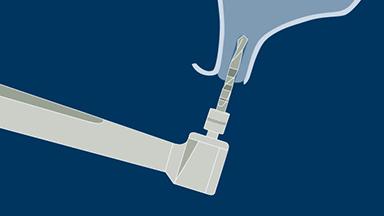

Implant Osteotomies

The implant osteotomy is a key surgical step in implant dentistry. It ends with the insertion of a dental implant that will later supply the patient with a fixed or removable replacement for missing teeth.

In this module we will first describe the correct bone preparation technique for implant placement. Subsequently, we will address the adjustments of the protocol that are necessary in different bone densities.